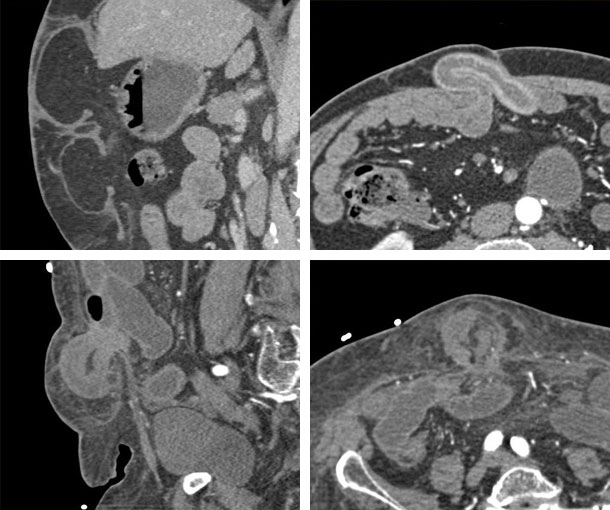

Ventral Hernia CT Findings

- Includes all hernias in anterior and lateral abdominal walls (excluding inguinal hernias)

- Large, typically defined as > 10cm

- Ratio of hernia sac volume to residual abdominopelvic cavity (“loss of domain”) of 20% or more

- Diaphragmatic descent